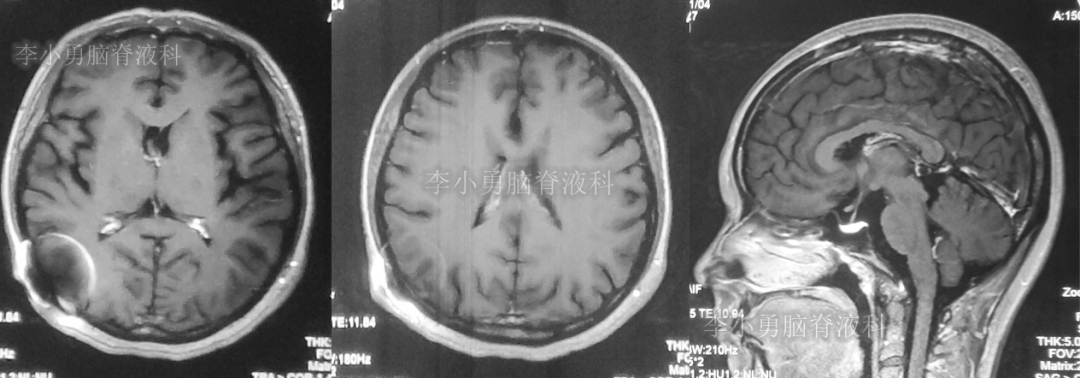

图-10:2019年10月26日头颅核磁

第5次调压后13天,即2019年11月4日,患者意识没有完全恢复正常,呈模糊状态,仅能完成简单的遵嘱动作,再次复查头颅核磁共振(图-11)见脑室较前明显缩小。

图-11:2019年11月4日头颅核磁